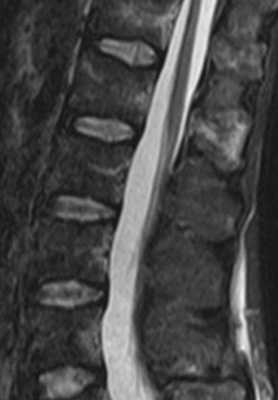

(Слева) На сагиттальном Т1-ВИ определяются признаки жировой перестройки костного мозга нижней половины тела Т5 и целиком тел и задних элементов Т6-Т8 позвонков. Обратите внимание на T9 позвонок, костный мозг которого практически полностью инфильтрирован опухолью.

(Справа) Сагиттальный срез, Т2-ВИ: признаки жировой перестройки костного мозга нижней половины тела Т5 и целиком тел и задних элементов Т6-Т8 позвонков. Костный мозг T9 позвонка инфильтрирован метастазом опухоли.

(Слева) На сагиттальном STIR МР-И у этого же пациента видно, что нормальный костный мозг и измененный в результате облучения костный мозг характеризуются практически одинаковой низкой интенсивностью сигнала, тогда как очаг метастатического поражения характеризуется высокой интенсивностью сигнала.

(Справа) На следующем сагиттальном FS T1-ВИ с КУ отмечается подавление сигнала и отсутствие контрастного усиления подвергшегося облучению и последующей жировой перестройке костного мозга нижней половины тела Т5 и тел и задних элементов Т6-Т8 позвонков. Тело T9 позвонка практически полностью замещено накапливающим контраст метастазом опухоли.